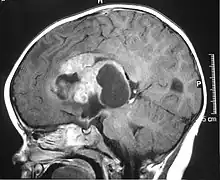

MRI of an AT/RT

The initial diagnosis of a tumor is made with a radiographic study (MRI[22] or CT-). If CT was performed first, an MRI is usually performed as the images are often more detailed and may reveal previously undetected metastatic tumors in other locations of the brain. In addition, an MRI of the spine is usually performed. The AT/RT tumor often spreads to the spine. AT/RT is difficult to diagnose only from radiographic study; usually, a pathologist must perform a cytological or genetic analysis.

Appearance on radiologic exam

AT/RTs can occur at any sites within the CNS; however, about 60% are located in the posterior fossa or cerebellar area. The ASCO study showed 52% posterior fossa; 39% sPNET; 5% pineal; 2% spinal, and 2% multifocal.[3]

The tumors' appearance on CT and MRI are not specific, tending towards large size, calcifications, necrosis (tissue death), and hemorrhage (bleeding). Radiological studies alone cannot identify AT/RT; a pathologist almost always has to evaluate a brain tissue sample.

The increased cellularity of the tumor may make the appearance on an uncontrasted CT to have increased attenuation. Solid parts of the tumor often enhance with contrast MRI finding on T1 and T2 weighted images are variable. Precontrast T2 weighted images may show an isosignal or slightly hypersignal. Solid components of the tumor may enhance with contrast, but not always. MRI studies appear to be more able to pick up metastatic foci in other intracranial locations, as well as intraspinal locations.